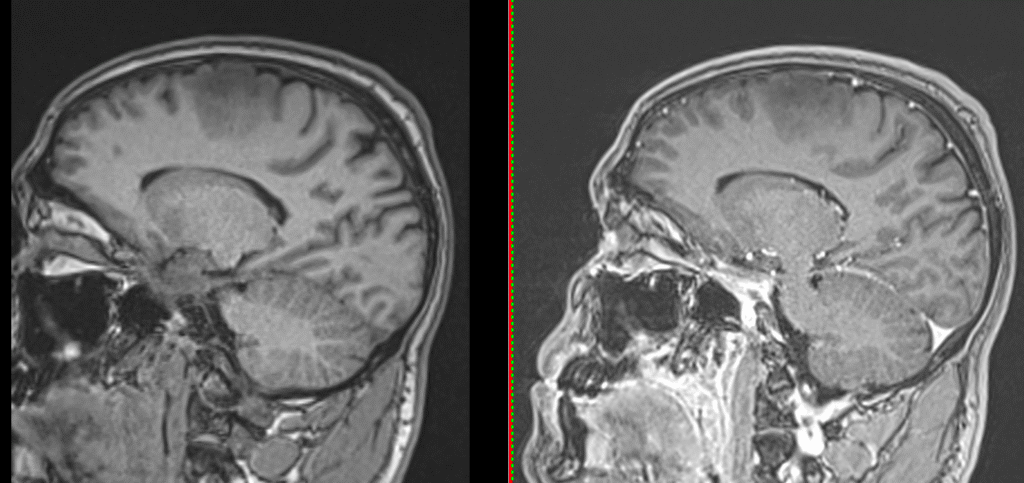

RMN cerebral cu contrast – metoda standard pentru caracterizarea glioamelor. Glioamele de grad mic apar ca leziuni hipointense pe T1, hiperintense pe T2, fără captare de contrast. În mod uzual se consideră că dacă un gliom de grad mic are o zonă cu priză de contrast pe RMN el este de grad III – anaplazic (grad înalt).